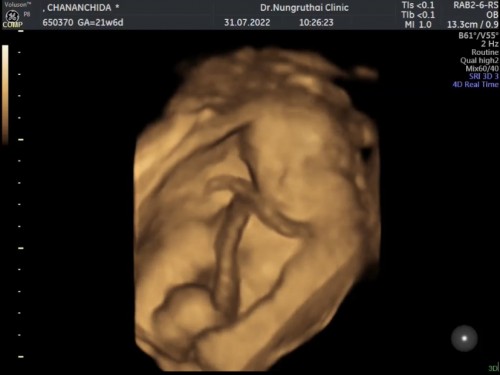

ท้องได้ 21+6 ค่ะ สายสะดือพันคอเป็นผ้าพันคอเลยค่ะ มีโอกาสที่จะหลุดออกมั้ยค่ะ พอดีหมอไม่ได้ว่ายังไงค่ะ แล้วอันตรายมากไหมค่ะ